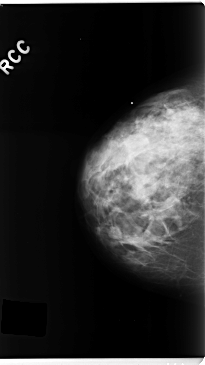

C_0272_1.RIGHT_MLO

RIGHT_CC LINES 4736 PIXELS_PER_LINE 2664 BITS_PER_PIXEL 12 RESOLUTION 50 NON_OVERLAY

RIGHT_MLO LINES 4712 PIXELS_PER_LINE 2688 BITS_PER_PIXEL 12 RESOLUTION 50 NON_OVERLAY